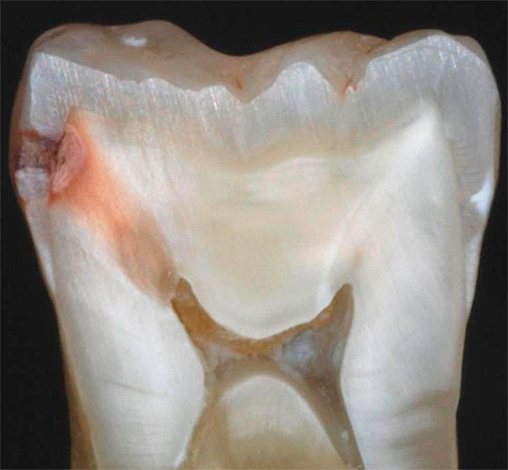

Nella foto sotto, la carie di smalto è presentata come la fase iniziale della lesione con segni caratteristici di questa particolare fase:

Molto spesso puoi osservare lesioni carie nascoste nel campo della fessura. È in queste numerose scanalature che si accumula facilmente la placca, che non può essere spazzolata a lungo. In alcuni casi, il suono di questi pozzi dà immediatamente una risposta, se c'è una rugosità, un difetto nascosto o una demineralizzazione iniziata negli strati sottosuolo.A volte possono esserci sensazioni dolorose a breve termine dal suono, ma il trattamento non può essere avviato senza diagnosi.